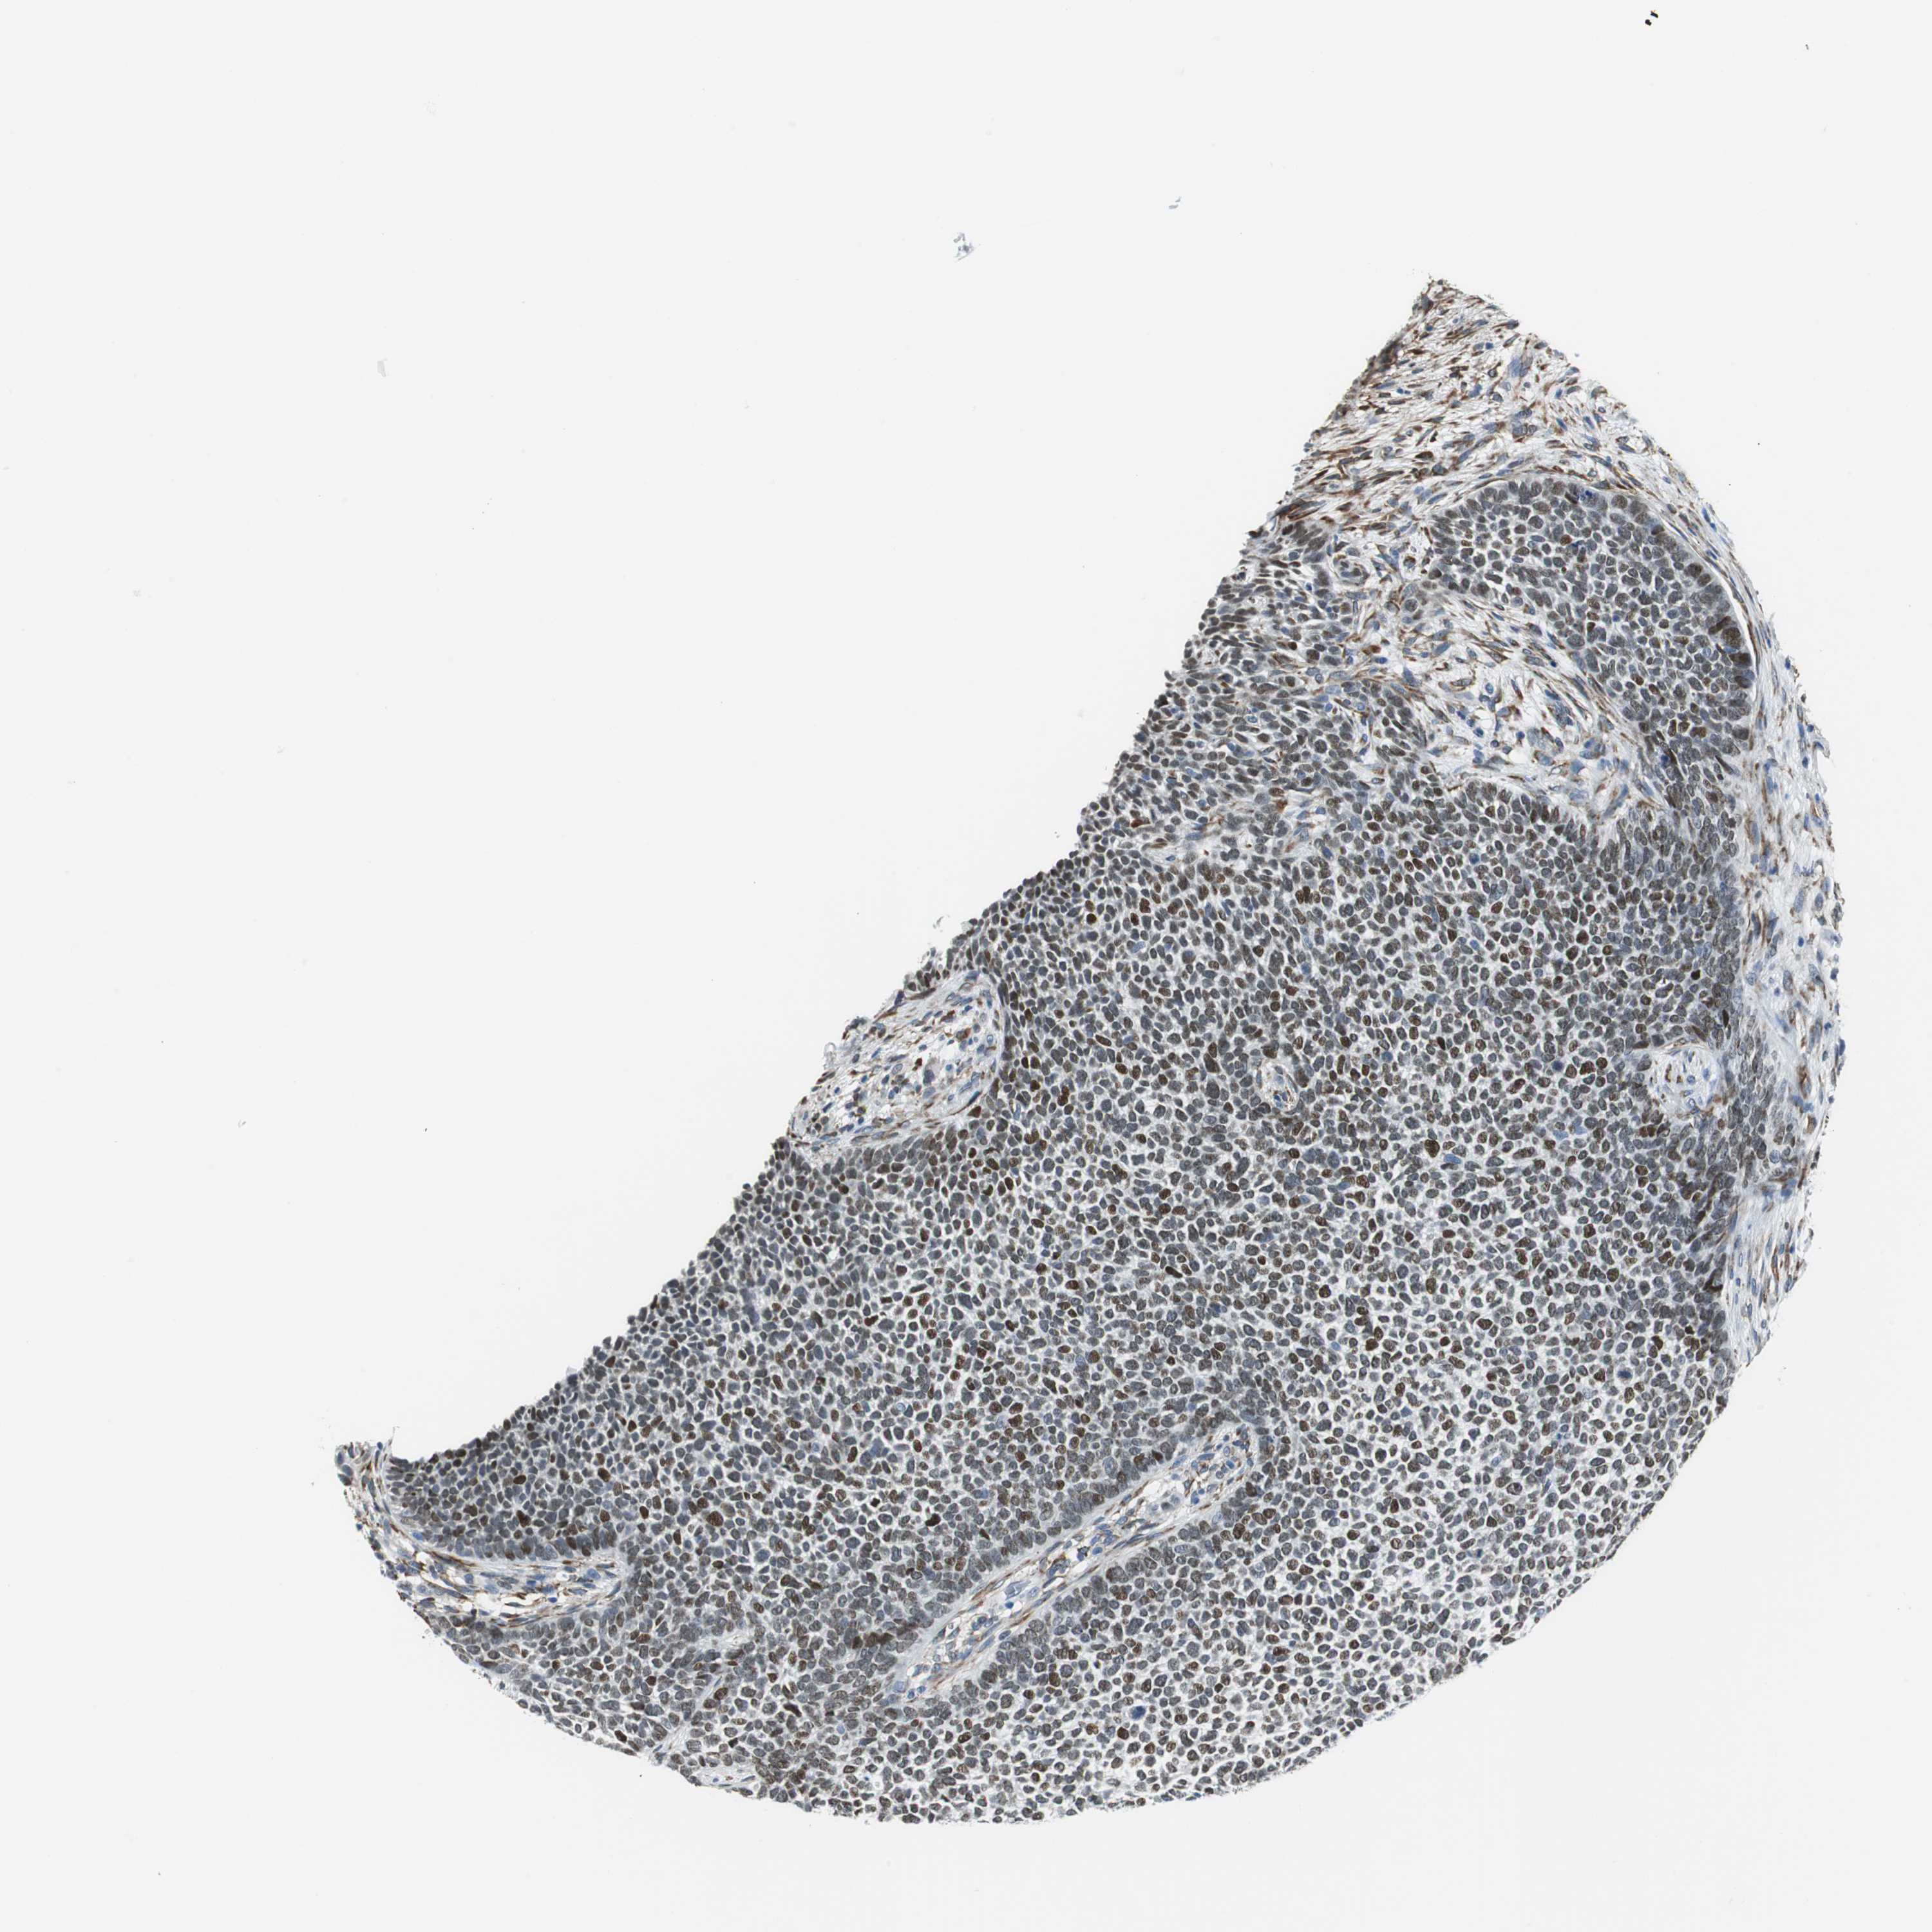

SKIN CANCER - Protein expressioni

A mouse-over function shows sample information and annotation data. Click on an image to view it in a full screen mode. Samples can be filtered based on level of antibody staining by selecting one or several of the following categories: high, medium, low and not detected. The assay and annotation is described here.

Antibody stainingi

Antibody staining in the annotated cell types in the current human tissue is reported as not detected, low, medium, or high, based on conventional immunohistochemistry profiling in selected tissues. This score is based on the combination of the staining intensity and fraction of stained cells.

Each image is clickable and will lead to virtual microscopy that enables deeper exploration of all samples and also displays staining intensity scores, fraction scores and subcellular localization as well as patient and tissue information for each sample.

Antibody HPA006465

Staining

High

Intensity

Strong

Quantity

>75%

Location

Nuclear

Squamous cell carcinoma, NOS